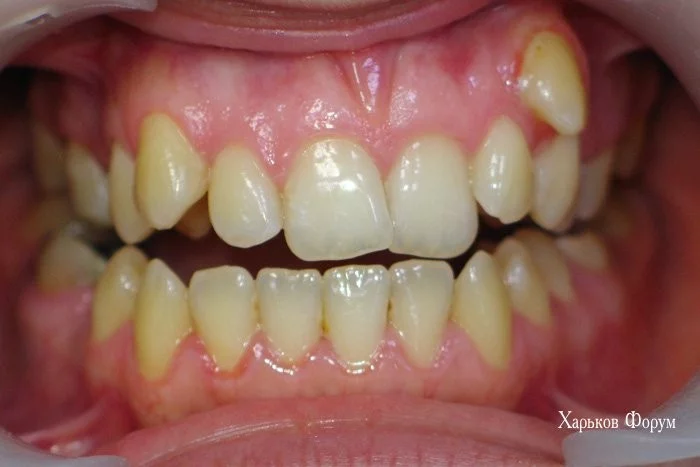

Я еще раз приложу снимки зубов ДО и ПОСЛЕ.

3. У Вас есть скученное положение зубов и дефицит места более 7 мм. А это железобетонное показание для лечения с удалением. Вы зря не взяли модели челюстей ДО лечения, для своего нового доктора! Они бы ему пригодились. Возможно, будут полезны фото

894a479df6110b7bc7b53.webp

ab37dc3d75222cee1.webp